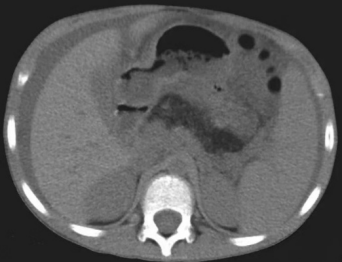

CT所示胰腺区脂肪密度影

该病十分罕见,患儿常以脂肪泻、肝酶异常为首发症状,随后会出现反复感染、生长缓慢、骨骼异常、血细胞减少等表现,需要通过大便脂肪含量、血清胰酶、胰腺影像学、骨髓细胞学分析及基因检测才能最终确诊。